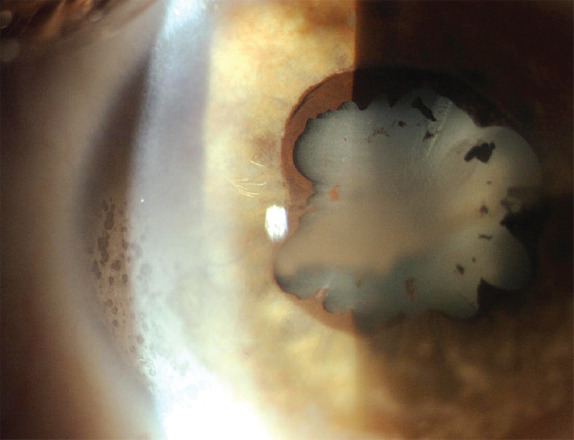

青少年特发性关节炎(JIA)是儿童中最常见的风湿病,由于其慢性性质和需要长期免疫抑制治疗,对身体和情绪造成重大挑战。葡萄膜炎是JIA最常见的关节外表现,可危及视力。尽管生物治疗取得了进展,但JIA仍然面临着巨大的治疗挑战,需要多次治疗尝试并密切监测继发性失败。jia相关性葡萄膜炎仍然是最具挑战性和侵袭性的葡萄膜炎类型之一,特别是在儿童中,由于其发病早,慢性,尽管有新的治疗方法,但治疗效果有限。早期识别和及时治疗关节炎和葡萄膜炎是实现持续缓解和预防并发症的必要条件。jia -葡萄膜炎的有效治疗需要儿科风湿病学家和眼科医生之间的合作,以确保及时评估,定期筛查和必要的治疗调整。这种综合护理方法对于实现最佳结果至关重要。因此,本文就JIA及其相关葡萄膜炎的发病机制、诊断和治疗进行综述。

Juvenile idiopathic arthritis (JIA) is the most common rheumatologic disorder in children, posing significant physical and emotional challenges due to its chronic nature and the need for prolonged immunosuppressive therapies. Uveitis is the most common extra-articular manifestation of JIA, and it can be a sight-threatening condition. Despite advances in biologic treatments, JIA continues to present substantial therapeutic challenges, necessitating multiple treatment attempts and close monitoring for secondary failures. JIA-associated uveitis remains one of the most challenging and aggressive types of uveitis, particularly in children, due to its early onset, chronicity, and limited therapeutic responses despite new treatments. Early recognition and prompt treatment of both arthritis and uveitis are essential for achieving sustained remission and preventing complications. Effective management of JIA-uveitis requires a collaborative approach between pediatric rheumatologists and ophthalmologists to ensure timely assessments, regular screenings, and necessary therapy adjustments. This integrated care approach is crucial for achieving optimal outcomes. Therefore, this review aims to extensively analyze the pathogenesis, diagnosis, and therapy of JIA and its associated uveitis.